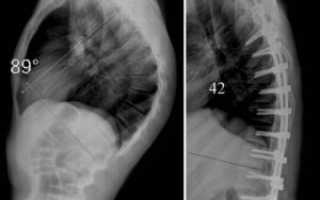

Если такими способами остановить прогрессирование болезни не удается, и угол изгиба превышает 70 градусов, показана операция на позвоночнике. Также хирургическое вмешательство оправдано при непрекращающемся болевом синдроме, серьезных нарушениях кровообращения, резком ухудшении работы органов дыхания. Выравнивание позвонков происходит за счет вживления специальных металлических конструкций.

К оперативному лечению прибегают при выраженном кифозе с углом более 60º, компрессии спинного мозга, стойком болевом синдроме. При этом возможно установление поддерживающих конструкций (мост) с частичной коррекцией искривления позвоночника, удаление грубо измененных позвонков и дисков.

Оперативное лечение требуется в ситуации, когда угол кифоза достигает 75 градусов. Кроме того, показаниями к операции выступают стойкий болевой синдром, не поддающийся купированию консервативными методами лечения, а также нарушение функций органов грудной клетки.

Хирургическое лечение болезни Шейермана-Мау предполагает выпрямление и укрепление позвоночного столба с помощью специальной металлической конструкции.